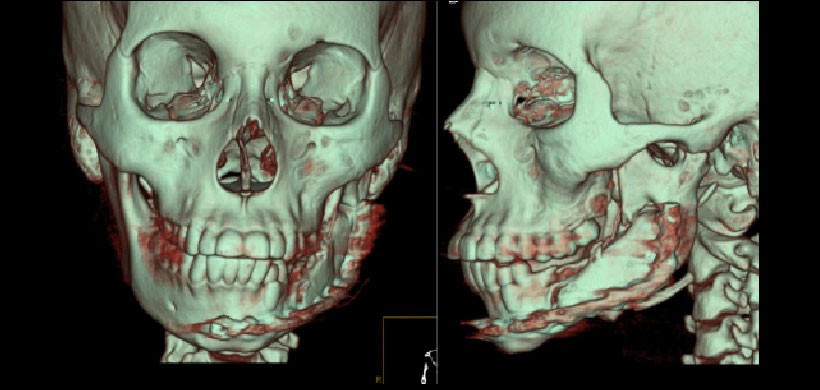

Fig 5. Control mediante tomografía de haz cónico  7 años posterior a la intervención. Se observa una simetría facial adecuada, una cicatriz casi imperceptible y la remodelación total del injerto.